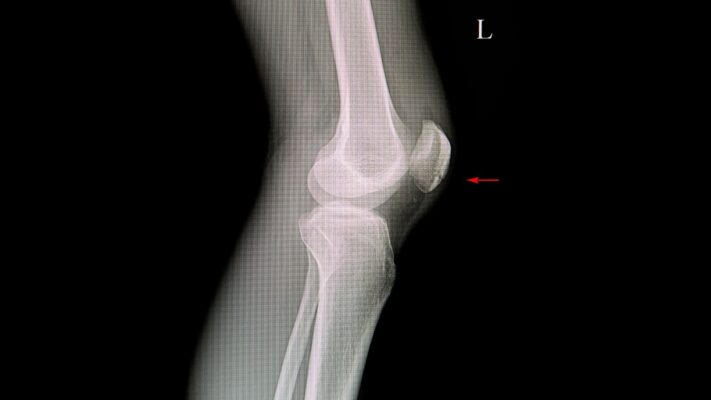

Fizik muayene çoğu zaman tanı için yeterli olsa da tanıyı kesinleştirmek, nöromanın boyutunu görmek ve diğer olası hastalıkları dışlamak için görüntüleme yöntemlerine başvurulur. Röntgen filmleri, yumuşak dokuyu (siniri) göstermez ancak kemik yapıyı değerlendirmek için mutlaka çekilir. Stres kırığı veya kireçlenme gibi kemiksel sorunları elemek için röntgen ilk basamaktır.

Yumuşak dokuyu değerlendirmek için kullanılan başlıca yöntemler şunlardır:

- Ultrasonografi

- Manyetik Rezonans Görüntüleme (MR)

Ultrason, hem pratik hem de dinamik bir inceleme imkanı sunar. Hekim ultrason probu ile bölgeyi incelerken aynı zamanda baskı uygulayarak sinirin hareketini ve sıkışmasını anlık olarak görebilir. Manyetik Rezonans (MR) ise daha detaylı bir haritalama sağlar. Özellikle cerrahi planlanan vakalarda veya tanının şüpheli olduğu durumlarda MR, bölgedeki tüm anatomik yapıları en ince ayrıntısına kadar gösterir. Ancak asemptomatik (şikayeti olmayan) kişilerde de MR’da nöroma benzeri görüntüler çıkabileceği unutulmamalı, görüntüleme bulguları mutlaka hastanın şikayetleri ile örtüşmelidir.